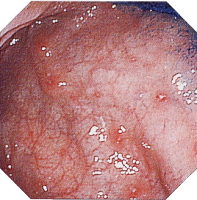

上部消化管病変(1) 上部消化管病変(2) 上部消化管病変(3)

クローン病画像 クローン病画像 クローン病画像

提供:牧山和也先生